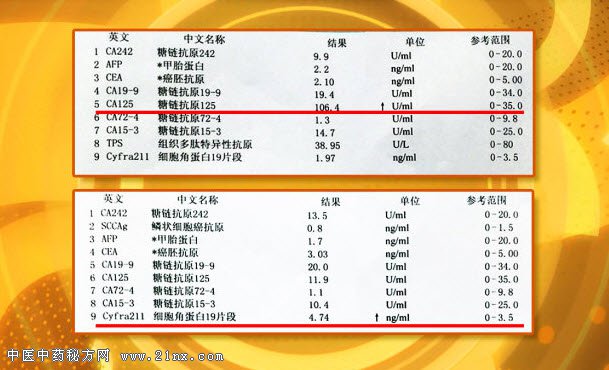

图:肿瘤标记物检查 如果不想做射线检查,肿瘤标记物检查是不是能提前筛查出肿瘤的存在,某一项肿瘤标记物升高,是不是一定预示某种癌症的发生?节目中将一一为您解答。 很多人可能都有类似的经历,在体检中发现结节、阴影。会立刻陷入恐慌,到底是不是癌?是不是凶多吉少?李单青主任把体检中经常遇到的问题分为如下几组情况:结节的多与少、大与小、以及是不是光滑。哪种情况最可能是真的患癌呢?